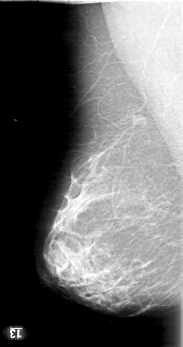

D_4004_1.LEFT_MLO

RIGHT_MLO LINES 5191 PIXELS_PER_LINE 2731 BITS_PER_PIXEL 12 RESOLUTION 43.5 NON_OVERLAY